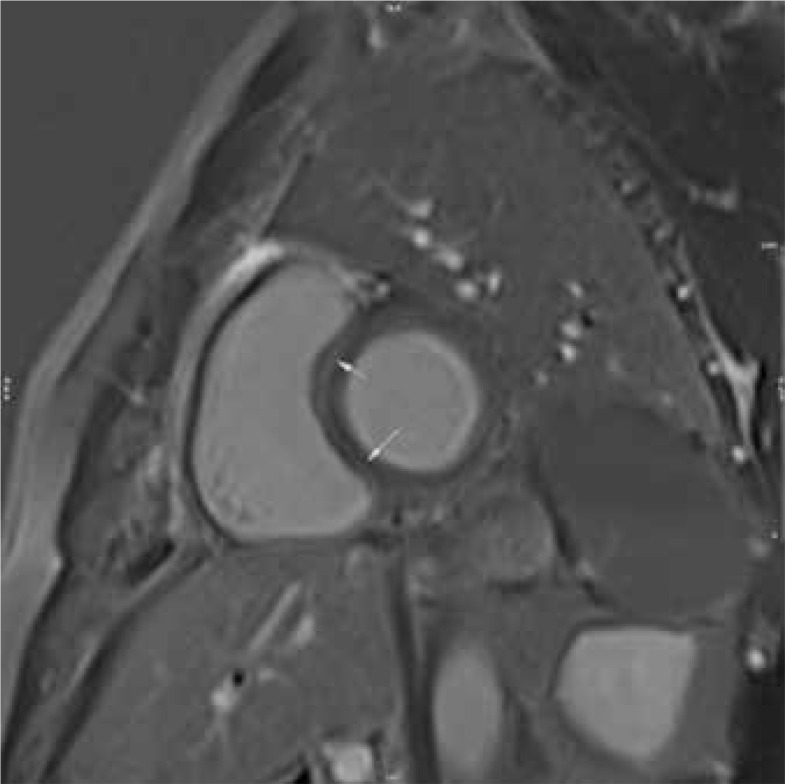

Purpose: Despite the low incidence of COVID myocarditis, its influence on outcomes is substantial. The pivotal role of cardiac magnetic resonance (CMR) in diagnosing myocarditis is considered to be associated with disease prognosis. The primary objective of this study was to conduct a comparative analysis of myocardial injury patterns, CMR pathologic features, outcomes, and their correlation with CMR findings in COVID- and non-COVID-related myocarditis.

Material and methods: This historical cohort study involved 124 patients diagnosed with myocarditis (COVID-19 or non-COVID-19), who underwent CMR between 2018 and 2021. The COVID group consisted of 70 individuals with a definite history of COVID-19 infection within 4 weeks, and the non-COVID group comprised 54 individuals who had no prior exposure to the SARS-CoV-2 virus. All patients were monitored for one year to assess the incidence of major adverse cardiovascular events (MACE). Additionally, baseline and follow-up echocardiography data were obtained with a minimum 3-month interval.

Results: In comparison between two groups regarding to indices of CMR, left ventricular (LV) ejection fraction (p < 0.001), right ventricular (RV) ejection fraction (p < 0.001) were significantly lower in non-COVID group, and significant LV and RV systolic dysfunction were meaningfully lower in the COVID group. Extension of late gadolinium enhancement (LGE) was significantly greater in COVID group. Finally, the incidence of MACE and mean event-free survival did not have significant difference between two groups.

Conclusions: Although CMR findings differed between the 2 groups, there was no significant difference in the risk of MACE or survival during one-year follow-up. Notably, LV and RV dysfunction were more prevalent in the non-COVID group, while extension of LGE was greater in the COVID group.